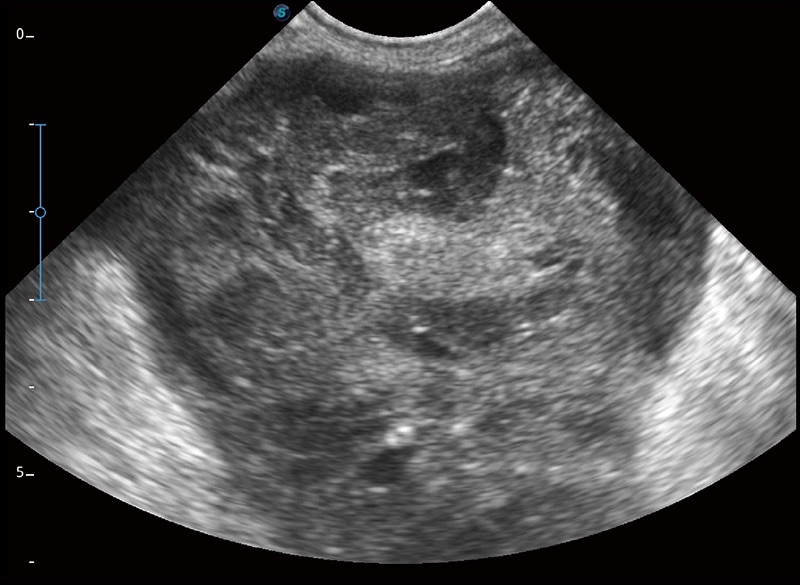

扩展成像

支持线阵和凸阵探头,一键操作即可获得更宽的图像视野

实时宽景成像

可实时观察感兴趣区域和病变位置